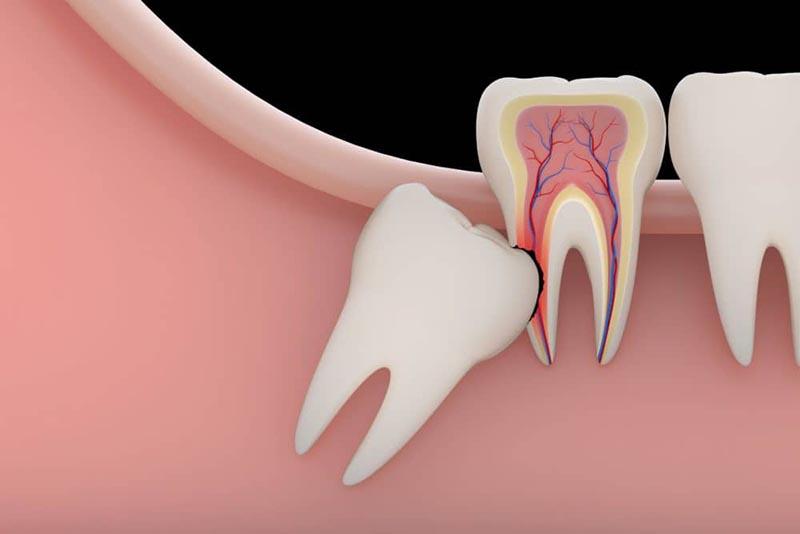

After the anesthesia takes its effect, the dentist will start the procedure of extraction. If it’s a simple extraction, the dentist will use dental tools to loosen the tooth and remove it completely. If it’s more complicated than that, a surgical extraction will be necessary. This can be done with the help of creating a hole at the gumline and completing the extraction from the inside. These type of complicated extractions are not only more expensive but also takes a much longer surgery time. Once the extraction is completed, your dentist will stop the excessive bleeding with the use of a pad.